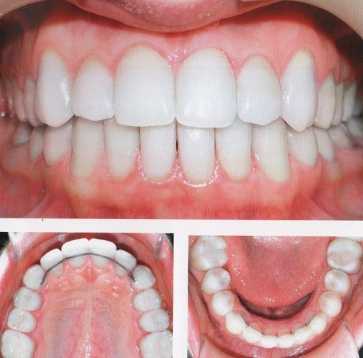

1) Стекловолокно. Это несъемный метод шинирования, к которому обращаться стали сравнительно недавно. Но на сегодня он очень популярен у пациентов, благодаря многим преимуществам. Стекловолокно в шинировании позволяет сохранить даже сильно расшатанные зубы, при этом почти не страдает их целостность.То есть, зубы не обтачивают и не депульпируют. Стекловолоконная шина не мешает гигиеническим процедурам, равномерно распределяет жевательную нагрузку между фиксированными зубами и отличается высокими эстетическими показателями.

Шинирование с помощью стекловолокна осуществляется в стоматологическом кабинете за один прием. Пациенту проводят местное обезболивание. Вдоль подвижных зубов, на внутренней стороне ряда на глубину 0,5 мм, проделывается бороздка для стекловолоконной нити, которая после укладки закрывается светоотверждаемым пломбировочным материалом. Свет превращает в балку композит со стекловолоконной нитью, благодаря которой зубы сцепливаются неподвижно вместе. Ответственный пациент, внимательно ухаживающий за полостью рта и следующий абсолютно всем советам стоматолога, может рассчитывать на 3-летний срок службы стекловолоконной шины. При этом ему нужно будет раз в год приходить к своему стоматологу для полировки конструкции. Не стоит шинировать передние зубы, если отсутствуют задние. Конструкция может сломаться из-за избыточной жевательной нагрузки на шинированный зубной ряд. Поэтому перед процедурой стекловолоконного шинирования необходимо навести порядок с прикусом и запротезировать недостающие зубные единицы.

Шинирование зубов стекловолокном

Стекловолоконное шинирование зубов это один из самых эстетичных и надежных методов.

Стекловолокно сохраняет даже сильно расшатанные зубы. С его помощью можно легко убрать зубные промежутки.

Для проведения шинирования стекловолокном не требуется обтачивать зубы и так же удалять из них нерв. Все это дает минимальное травмирование ротовой полости.

Шинирование подвижных зубов стекловолокном

Стекловолокно применяют при несъемных методах шинирования. Данная технология возникла относительно недавно и сразу же завоевала популярность благодаря большому числу преимуществ. Шинирование стекловолокном позволяет:

сохранить очень подвижные зубы;

избежать обтачивания зуба и депульпации;

качественно проводить гигиенические процедуры;

равномерно распределять между шинированными зубами нагрузку при жевании;

Процесс шинирования зубов проводится под местной анестезией. При правильном уходе шина из стекловолокна может прослужить до 3 лет.

Шинирование с использованием стекловолокна

Стекловолоконное шинирование относится к списку самых распространенных методов. Обычно оно используется в том случае, когда нужно соединить несколько зубов и максимально сэкономить. Длительность использования одной шины не превышает два года - после этого периода нужно будет устанавливать новую.

Весь процесс установки не занимает больше двух часов. Сначала нужно выполнить очистку эмали, потом создать на ней небольшую борозду. После этого лента из стекловолокна фиксируется на композитные материалы. После того как конструкция отшлифована, врач убедился, что пациенту ничего не мешает, работа считается завершенной.

Эта методика нужна для того, чтобы выполнить шинирование зубов при заболевании пародонта. В пользу выбора такого метода говорит высокий уровень прочности, хорошая совместимость с зубными тканями и доступность по цене.